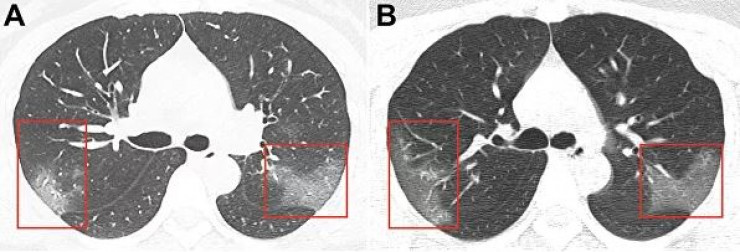

Изображения, опубликованные в журнале Radiology, получены в результате компьютерной томографии 33-летней женщины, госпитализированной в китайском городе Ланьчжоу с температурой 39 градусов.

На первом снимке видны помутнения, создающие "эффект матового стекла". На втором, сделанном три дня спустя, можно заметить, что пораженная область расширяется.

"На основании эпидемиологических характеристик, клинических проявлений, изображений грудной клетки и лабораторных данных был поставлен диагноз: "пневмония 2019-nСоV", - говорится в публикации.